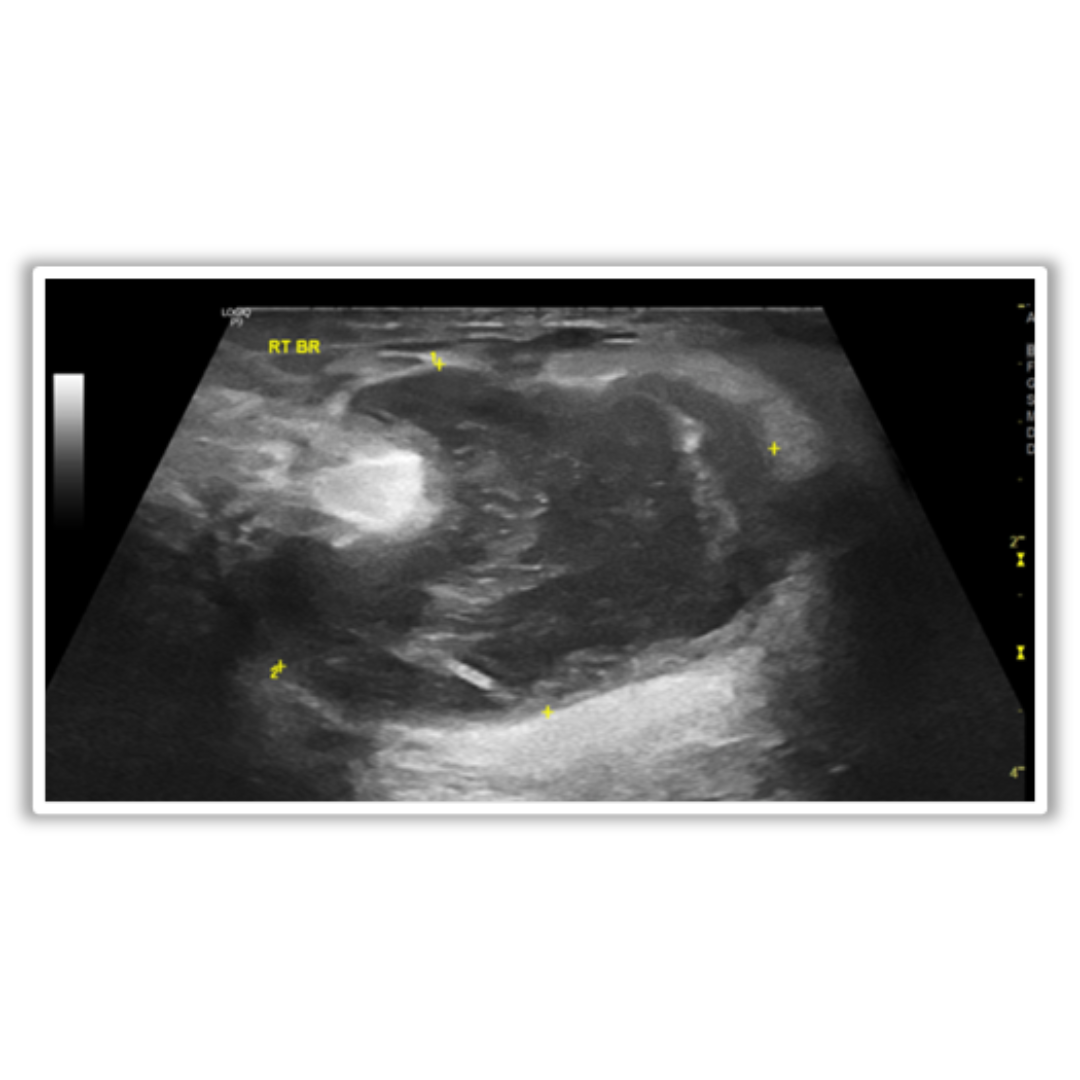

Imagen 2: Se observan en la región retroareolar derecha dos nódulos sólidos intraductales de 2 y 6 mm, que muestran vascularidad periférica a la aplicación Doppler color.